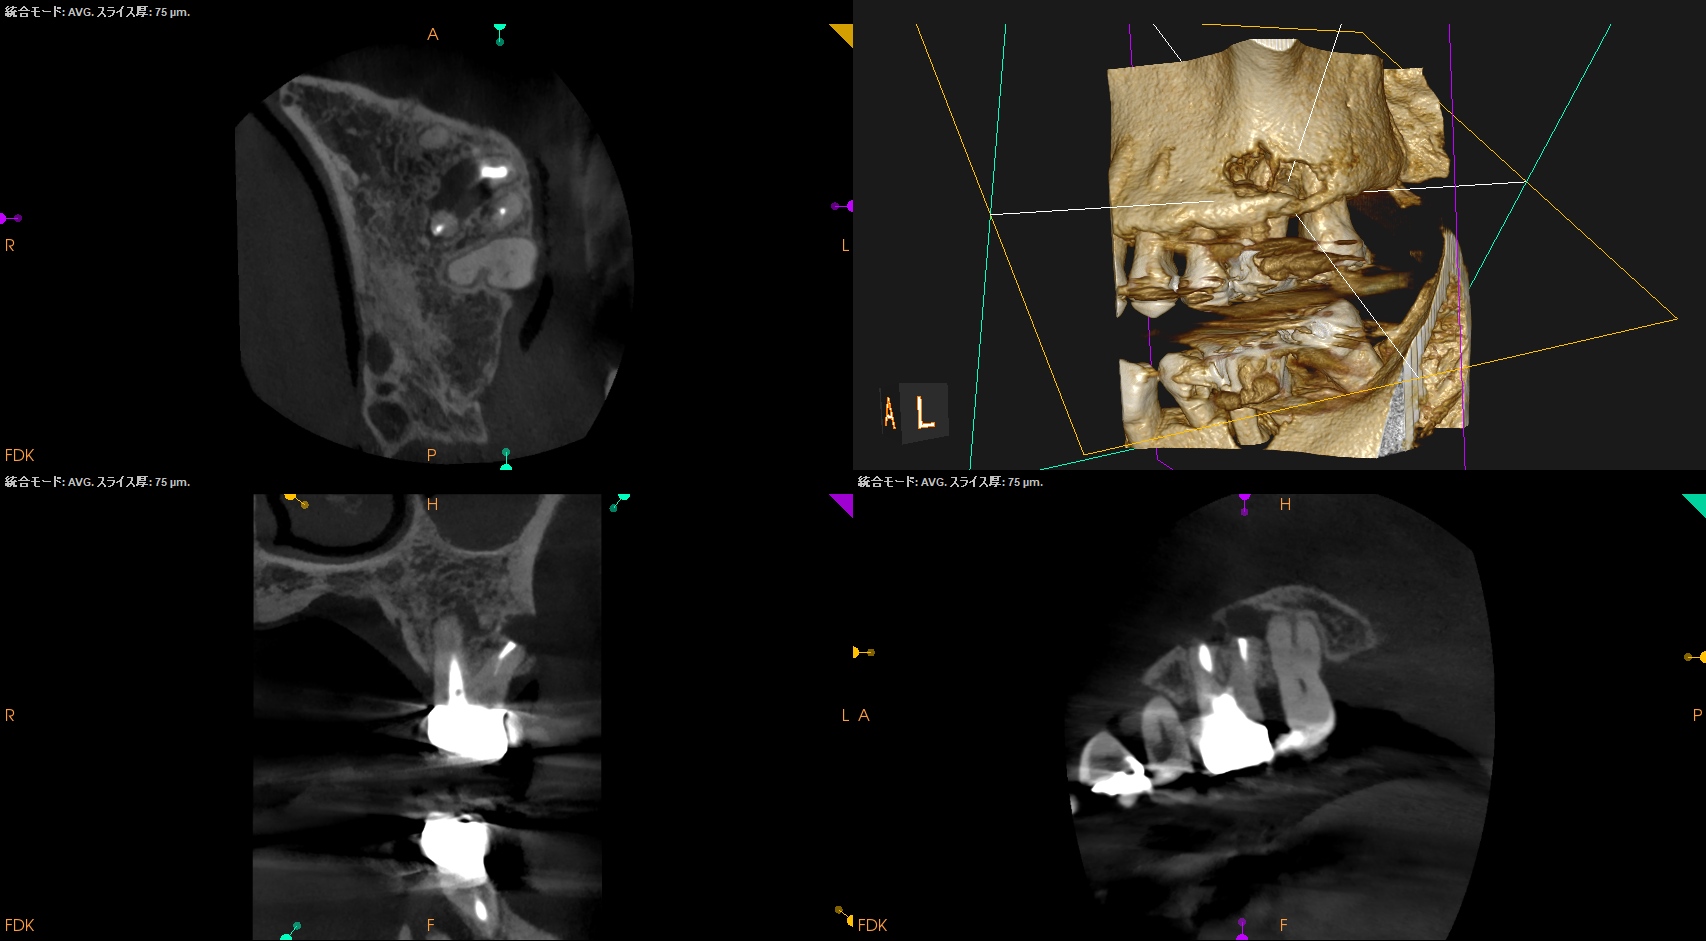

DBは楽だが、MBは頬舌径が7.4mmでMB1, MB2があるという…難ケースだ。

#14 MB,DB Apicoectomy(2026.2.12)

逆根充後にPA, CBCTを撮影した。